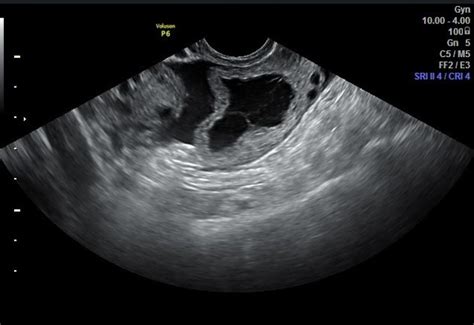

An ovarian cyst is a fluid-filled sac that forms on an ovary. While they’re common—especially during reproductive years—rupture occurs when the cyst bursts, releasing its contents and potentially triggering internal bleeding, pain, and serious complications. Unlike typical cysts that may go unnoticed, a ruptured cyst can cause sudden, severe discomfort, fever, nausea, and bleeding that demands urgent medical attention.